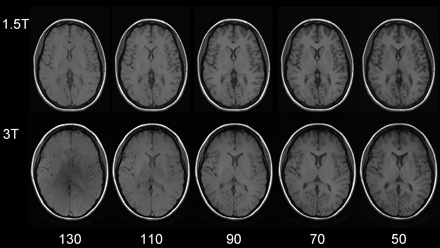

Apparently, gray-to-white matter contrast is reduced in spin-echo T1 imaging at 3T (30) when compared with 1.5T (Fig 6). There are several factors contributing to this observation. T1 times of gray and white matter lengthen and converge at higher fields (31–33). Moreover, shielding effects induced by eddy currents prevent central parts of the image from being properly excited (16), which results in reduced signal intensity of the basal ganglia region. In addition, magnetization transfer effects are enhanced at higher B0, thus reducing signal intensity and contrast. There are several ways to compensate for these effects. For example, inversion recovery sequences appear very well suited if one is only interested in increasing gray to white matter contrast (Fig 7). The inversion pulse, however, interferes with visualization of contrast enhancement following gadolinium administration. Enhancing lesions may not be visible (Fig 8), because in inversion recovery sequences, unlike conventional T1 spin-echo sequences, the tissue with the shortest T1 does not necessarily exhibit the brightest signal intensity, depending on T1. Therefore, inversion recovery sequences are not quite useful for comparative pre- and postcontrast T1 spin-echo imaging, regardless of B0. A different approach to increase gray-to-white matter contrast during T1-weighted spin-echo imaging at both field strengths is to reduce the excitation flip angle (34). Although this reduces SNR slightly, the gain in gray-to-white matter contrast is obvious and more pronounced at 3T (Fig 9). The effect can be predicted from theoretical calculations (35) by using known T1 and T2 relaxation times of gray and white matter (33) but is empirically larger than the theoretical predictions at 3T, probably because of shielding and magnetization transfer effects (34).

Same section position with spin-echo T1-weighted sequences at 1.5T (upper row: TR, 700 ms; TE, 10 ms; section thickness, 5 mm; matrix, 256 × 192; FOV, 220 × 220 mm2; bandwidth, 200 Hz/pixel) and 3T (lower row: same imaging parameters). Flip angles decreasing from left to right 130°, 110°, 90°, 70°, 50°. The lowest flip angle shows the best gray-to-white matter contrast. The effect is stronger at higher field.